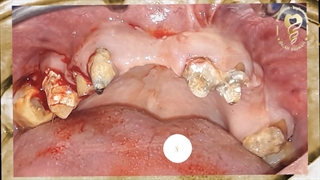

خانمی با مشکل فاصله زیاد دندانها و کمبود مادرزادی یک دندان مراجعه کرده است.

درمان ارتودنسی ثابت در فک بالا برای تنظیم فضا انجام شده و یک ایمپلنت بجای دندان شماره 2 قرار داده شده است.